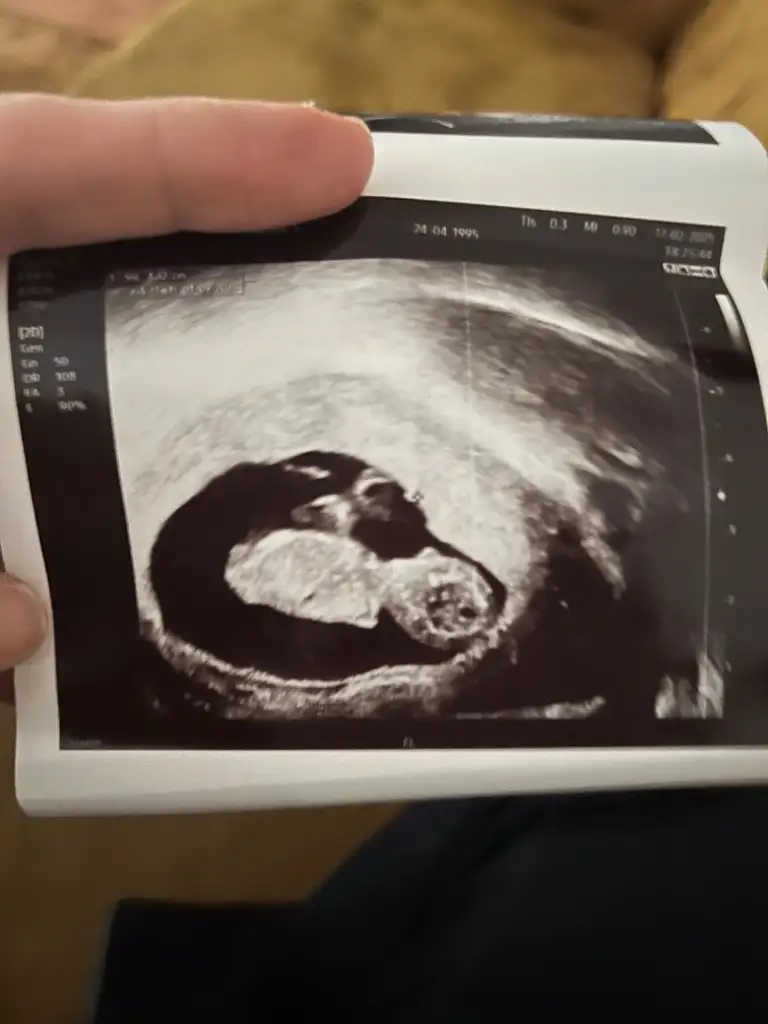

her şey yolundaymiş :)) büyük ihtimalle kız ama değişebilir kesin demek için erken dedi. Bacak arası kız gibi gözüküyor dedi.